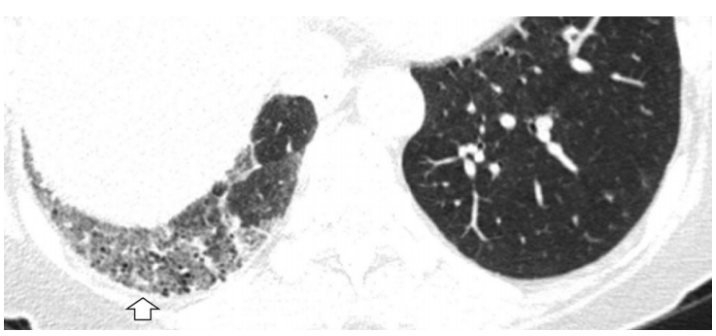

(1)感染性疾病:病毒性?细菌性?真菌?非典型病原体?吸入性肺炎?(2)非感染性疾病:心衰?急性肺栓塞?自身免疫性疾病?麻醉/手术相关肺损伤?急性间质性肺炎?回顾分析患者入院时胸部CT: 双肺靠近外周近胸膜处有轻微细小间质样改变(图4)。诊断:急性间质性肺炎;Ⅰ型呼吸衰竭;左肺下叶部分切除术后;高血压病。ECMO支持;呼吸机支持;甲泼尼松80 mg q12h,尼达尼布;镇静镇痛;抗感染;营养支持。ECMO第6天, 术后第18天, 肺部病变进一步加重(图5)。血气分析: pH 7.543, PaO2 154 mmHg, PaCO2 33.2 mmHg(ECMO, FiO2 100%, MV FiO2 60%)。术后第26天复查胸部CT未见改善。患者最终死亡。笔者团队也曾接诊过一例早期肺癌患者,2013年和2014年随访肺部结节均无明显变化。2015年胸部手术后2天,两肺变白(图6)。当时医生警惕性非常高,立刻行胸部CT检查并予相应治疗,患者最终存活。2022年RadioGraphics 杂志报道一例85岁女性腺癌患者奥希替尼治疗5个月后。图7-A和B为治疗前胸部CT图像,可见右肺中叶有肿块(A中箭头)。胸膜下区域磨玻璃改变和网状结构(箭头)提示存在间质性肺异常(Interstitial Lung Abnormalities,ILA)。治疗5个月后的轴位CT图像显示肿块(C中白色箭头)、弥漫性磨玻璃改变和合并症(黑色箭头)。图源:Radiographics, 2022, 42(7):1925-1939.另一例66岁右上肺鳞癌患者,术前CT显示肿块(图8-A中箭头)位于肺右上叶。轻度磨玻璃改变(箭头),提示ILA,见于胸膜下区域。图8-C和D为术后CT,显示弥漫性磨玻璃样改变和实变(箭头),牵引性支气管扩张症(图8-C中箭头),也可见胸腔积液(图8-D中箭头)。图源:Radiographics, 2022, 42(7):1925-1939.